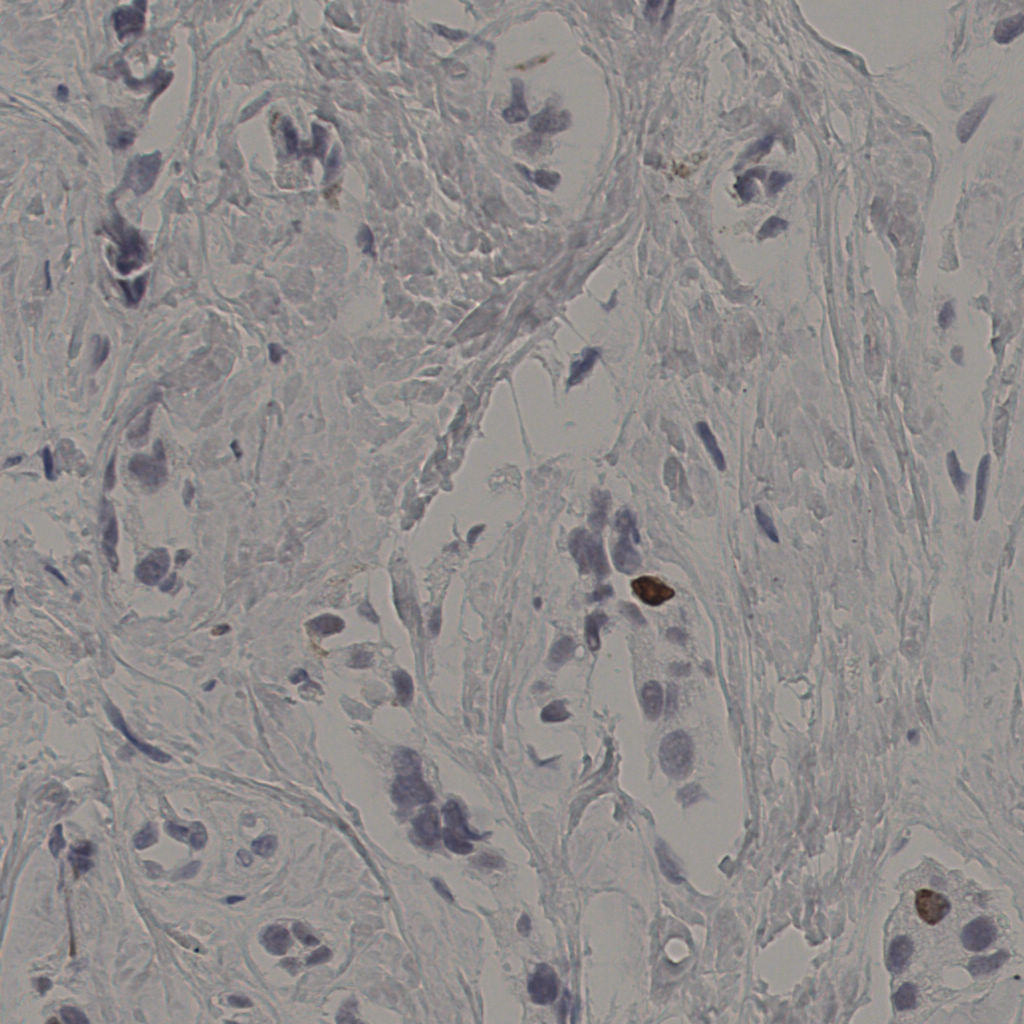

5.31%

Ki67 指数

阴 19502

阳 1093

切片统计

总切片

2970

有效

554

已标记

554

有效率

19%